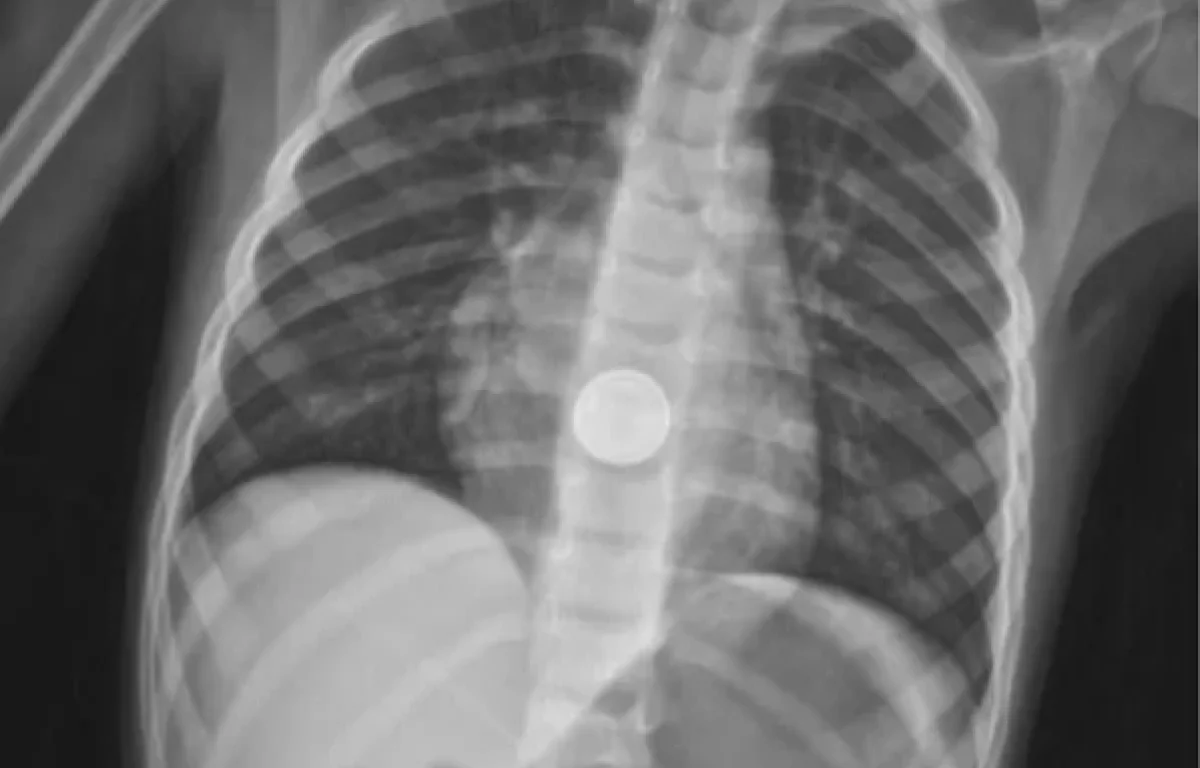

בצילום רנטגן שבוצע במיון הילדים, נצפתה הסוללה בצורה ברורה - והוזעק מיד צוות החירום של מחלקת גסטרואנטרולוגיה ילדים, בראשות ד"ר זאב דוידוביץ. בהובלתו, יחד עם המרדים ד"ר עומר רמדאן ובליווי צוות חדר הניתוח, בוצעה אנדוסקופיה דחופה תחת הרדמה כללית, שהובילה לשליפת הסוללה.